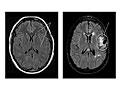

Magnetic Resonance Imaging (MRI) of the Head

Magnetic resonance imaging (MRI) is a test that uses a magnetic field and pulses of radio wave energy to take pictures of the head. In many cases, MRI gives information that can't be seen on an X-ray, ultrasound, or computed tomography (CT) scan.

For an MRI of the head, you lie with your head inside a special machine (scanner) that has a strong magnet. The MRI can show tissue damage or disease, such as infection or inflammation, or a tumor, stroke, or seizure. Information from an MRI can be saved and stored on a computer for more study. Photographs or films of certain views can also be made.